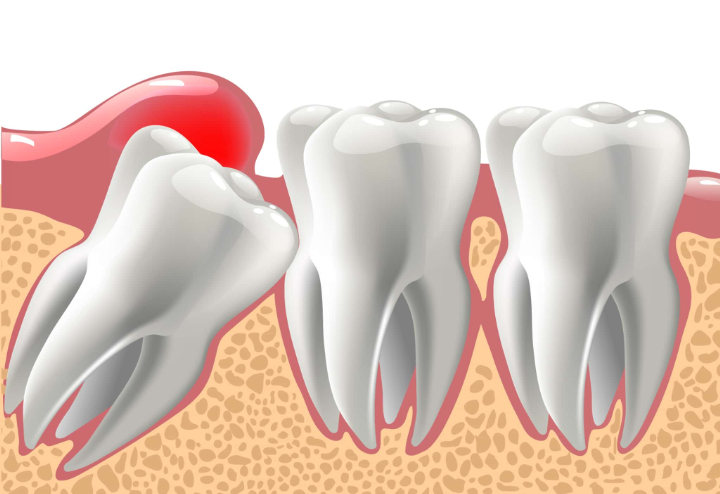

虫歯や炎症を繰り返している

親知らずの歯冠の一部のみ歯茎から出ている半埋伏の状態では、汚れや細菌が溜まりやすくなります。また、親知らずは歯列の最も後ろに位置するため、歯磨きも上手くできないケースが少なくありません。このため、虫歯や智歯周囲炎を繰り返す方も多いです。

智歯周囲炎は、親知らず(智歯)の周りの歯茎が炎症を起こした状態です。虫歯も智歯周囲炎も、重症化すると歯を失う可能性があるだけでなく、手前の奥歯(第二大臼歯)の健康を損ねる可能性も否定できません。

さらに、親知らずは口内の奥まった場所にあるため、治療が難しいこともあります。しっかりと治療できなければ、トラブルを繰り返して他の歯に影響が出るケースもあるため、虫歯や炎症が発生している場合では、親知らずの抜歯を検討することが多いです。

親知らずがまっすぐ生えていない場合、隣の歯を押して歯並び全体を乱す可能性があります。親知らずはまっすぐ生えることが少なく、斜めや横向きに生える方が非常に多いです。

斜めや横向きに生えると、後ろから歯列を押す力がかかり、一部の歯が歯列から飛び出してしまうことがあるのです。